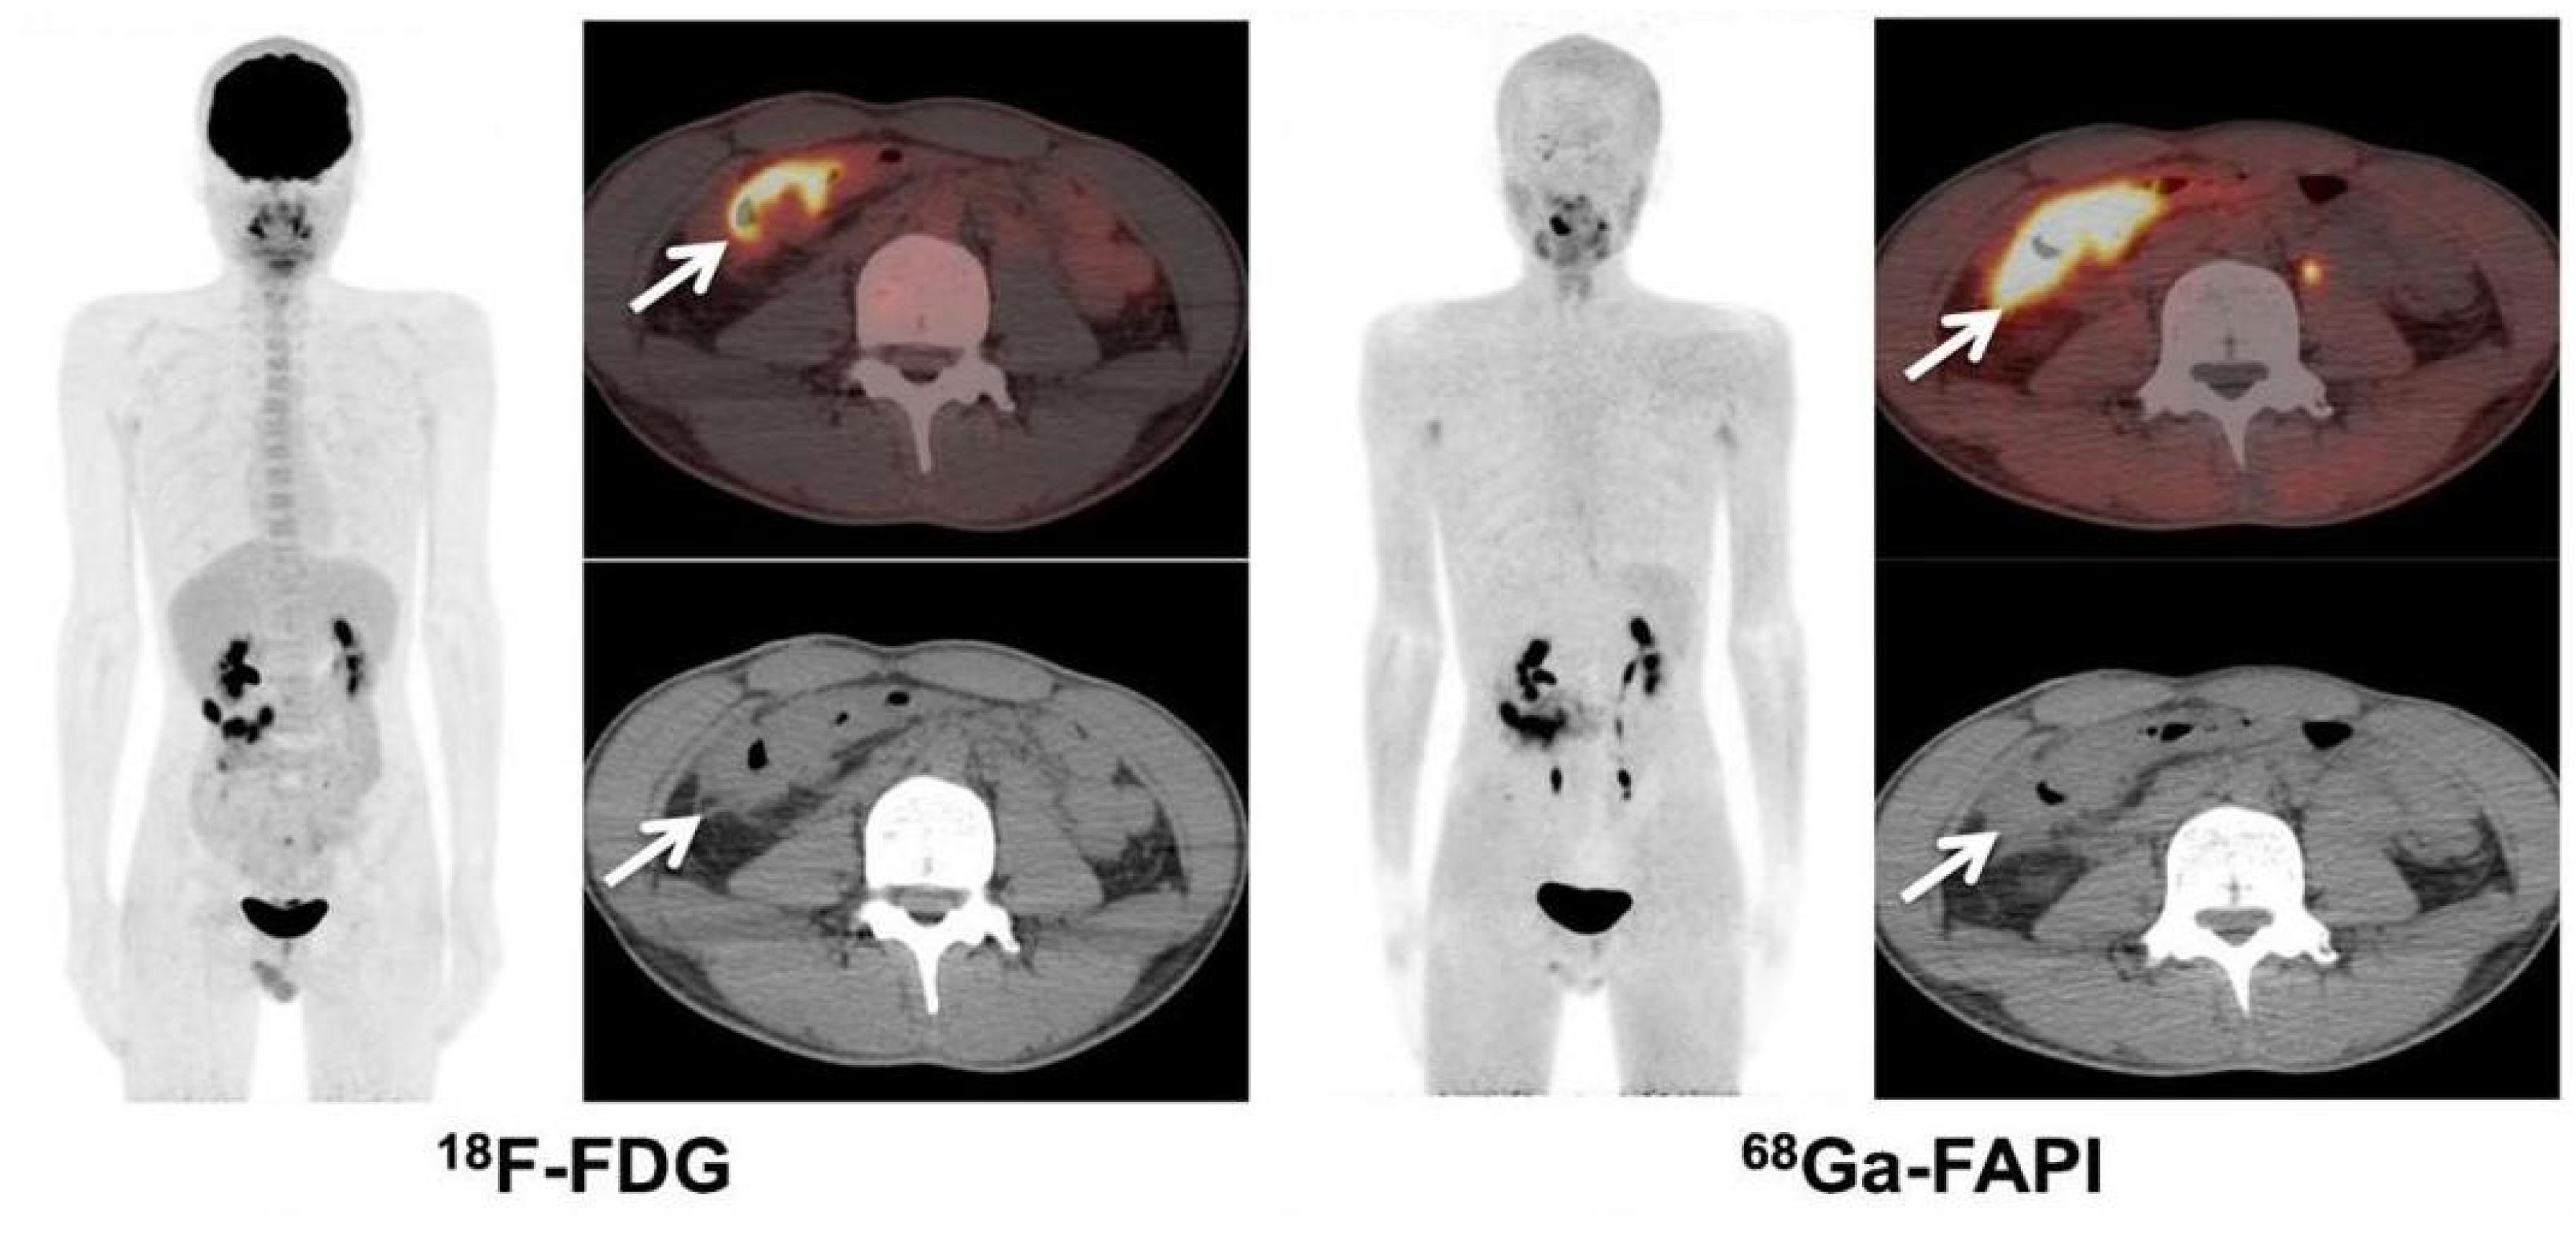

- Güzel, Y.; Kaplan, İ.; Kepenek, F.; Söğütçü, N.; Kömek, H. Perirenal Infiltration of Signet Ring Cell Colon Carcinoma Shown by 68Ga-FAPI PET/CT. Clin. Nucl. Med. 2022, 47, e509–e512. [Google Scholar] [CrossRef] [PubMed]

| Güzel et al. | 2022 | Case | 68Ga-FAPI was superior to 18F-FDG in evaluating recurrent signet ring cell colon cancer. |